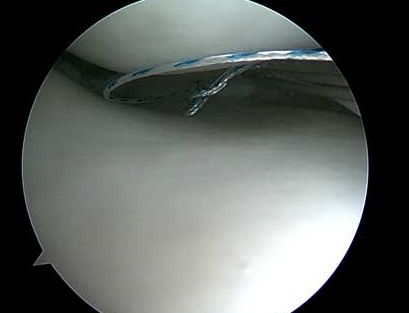

Meniskimplantat/Menisktransplantation

Vid stora komplexa skador på menisken är det vanligt att stora delar av menisken måste tas bort.

Det pågår forskning med konstgjorda meniskimplantat. Men även menisktransplantationer, där man använder menisker från avlidna.

Erfarenheterna i Norden av dessa metoder är begränsade och det betecknas som experimentell kirurgi.